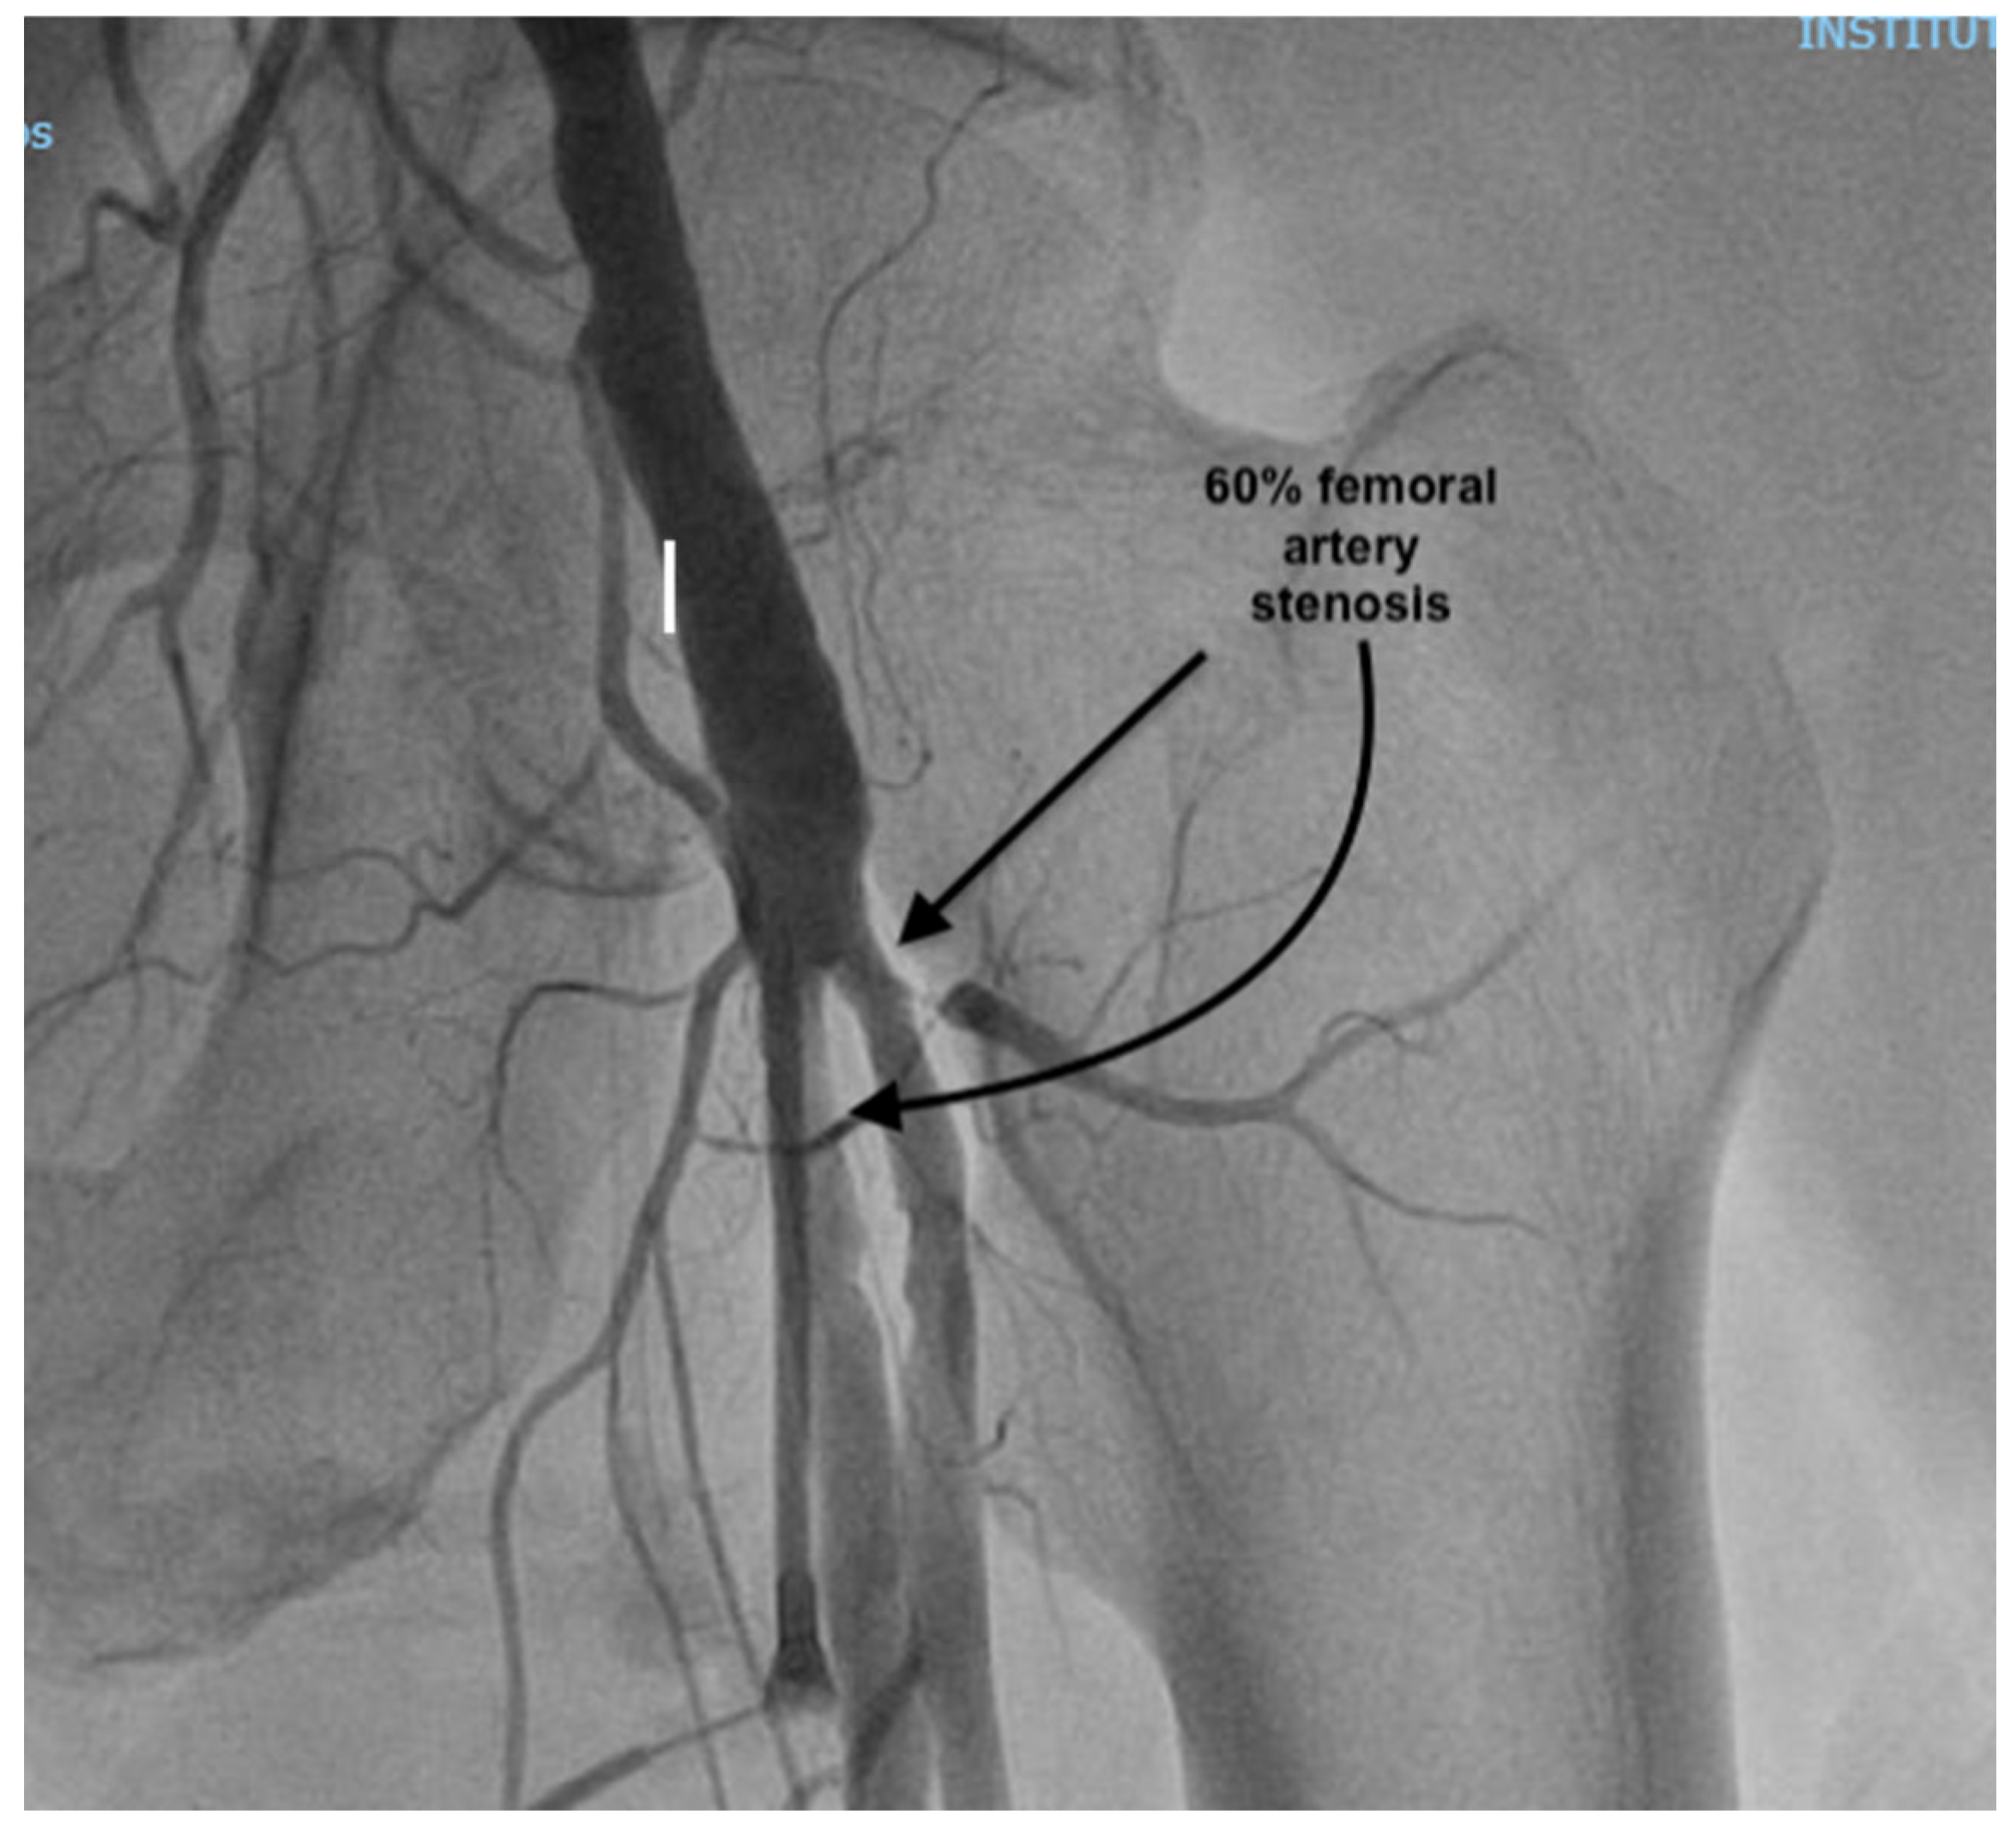

Figure 2. Peripheral angiography prior to IABP placement, showing 60% stenosis of superficial femoral artery and profonda femoris artery.

At presentation, the patient was in cardiogenic shock, at Society for Cardiovascular Angiography and Interventions (SCAI) stage C, with acute pulmonary edema: he was dyspneic, with a breathing rate of 25/min; an SpO2 of 90% under 6 L/min of oxygen, with diffuse fine crackles in both lungs; a blood pressure (BP) of 120/80 mmHg; a heart rate of (HR) 120/min; warm, but clammy skin; and a serum lactate of 2.5 mmol/L. He had a loud holosystolic murmur at cardiac auscultation. The ECG showed inferior ST-elevation myocardial infarction (STEMI), and the fast trans-thoracic echocardiography (TTE) showed moderate left ventricular (LV) dysfunction, with an ejection fraction (EF) of 40%, a moderate MR (vena contracta 6 mm), and a large VSD (2 cm), with left-to-right shunting. The patient was taken to the cardiac catheterization laboratory, where a right coronary artery (RCA) sub-occlusion was diagnosed (Figure 1), with no other hemodynamically significant coronary lesions. During the procedure, the patient was managed using non-invasive pressure-support mechanical ventilation (NIV) due to aggravated dyspnea and orthopnea. Interventional revascularization was not possible or indicated due to the distal lesions, with TIMI II flow, and the lack of benefit in an already non-viable myocardial territory. Despite significant PAD of the left inferior limb (Figure 2), an intra-aortic balloon pump (IABP) via the superficial left femoral artery was placed immediately.